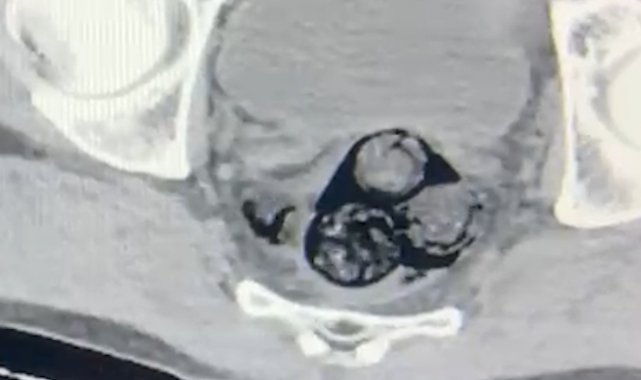

Iğdır İl Emniyet Müdürlüğü Narkotik Suçlarla Mücadele Şube Müdürlüğü ekipleri, yurt dışından Türkiye'ye giriş yapan ve şüpheli hareketler sergileyen A.İ. isimli kişiyi takibe aldı. Yapılan detaylı aramalar neticesinde, şahsın vücut boşluklarında uyuşturucu madde taşıdığı belirlendi. Radyolojik görüntüleme sonucu, şüphelinin makat bölgesinde dört farklı yabancı cisim olduğu ortaya çıktı. Sağlık kontrolünden geçirilerek, çıkarılan cisimlerin içinde toplamda 140 gram metamfetamin olduğu tespit edildi. Uyuşturucu madde taşımak ve ticaretini yapmak suçundan hakkında işlem başlatılan A.İ., Iğdır Adliyesi'ne sevk edildi. Mahkemeye çıkarılan şahıs, tutuklanarak cezaevine gönderildi.